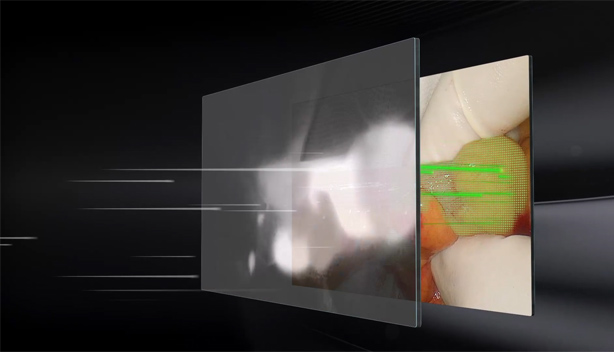

FusiĂłn de fluorescencias a nivel de pĂxel

El estricto control del proceso de montaje ayuda a obtener la fusiĂłn y alineaciĂłn pĂxel a pĂxel de la imagen de luz blanca y fluorescencias. La imagen de fluorescencias con detalles de textura de luz blanca tambiĂ©n puede ayudar en todo el proceso quirĂșrgico guiado por fluorescencia